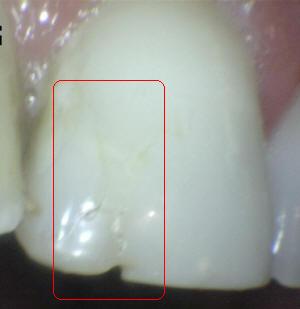

¿Determine los códigos pertinentes a cada imagen?

Click en el hipervínculo: Para comparar el resultado de su diagnóstico